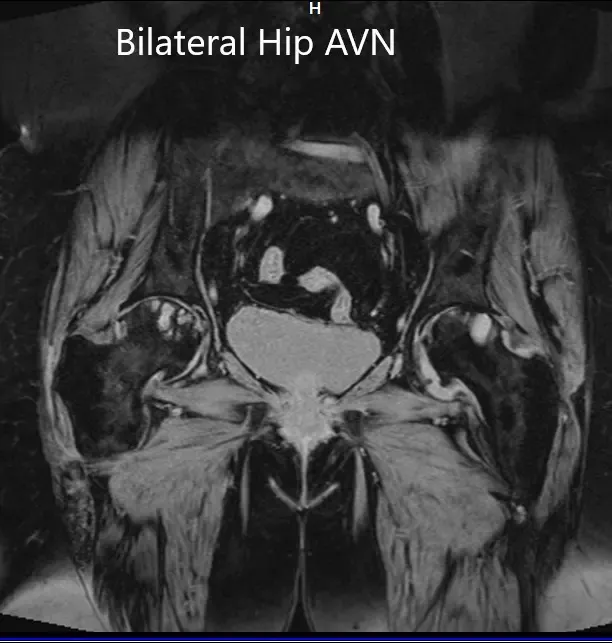

MRI was obtained which showed:

Right Hip Joint: There is a loss of sphericity of right femoral head, involving more than 2/3 of the circumference. In the superior part of the right femoral head, a focal lesion is visualized which is bounded by a serpiginous T1 hypointense margin. The lesion is hypointense on both T1 & T2WI relative to the marrow (Mitchell class – D).

No subchondral fracture is detected. A minimal amount of fluid is seen in the joint cavity. The femoral neck and acetabulum display normal signal intensity. Muscles in view display normal signal intensity.

Left hip joint: Displays similar although less severe changes. The sphericity of the left femoral head is maintained. There is more than 2/3 circumferential involvement of the left femoral head. No subchondral fracture is seen. No joint effusion is seen.

Coronal section of T2WI and T1WI of pelvis MRI.